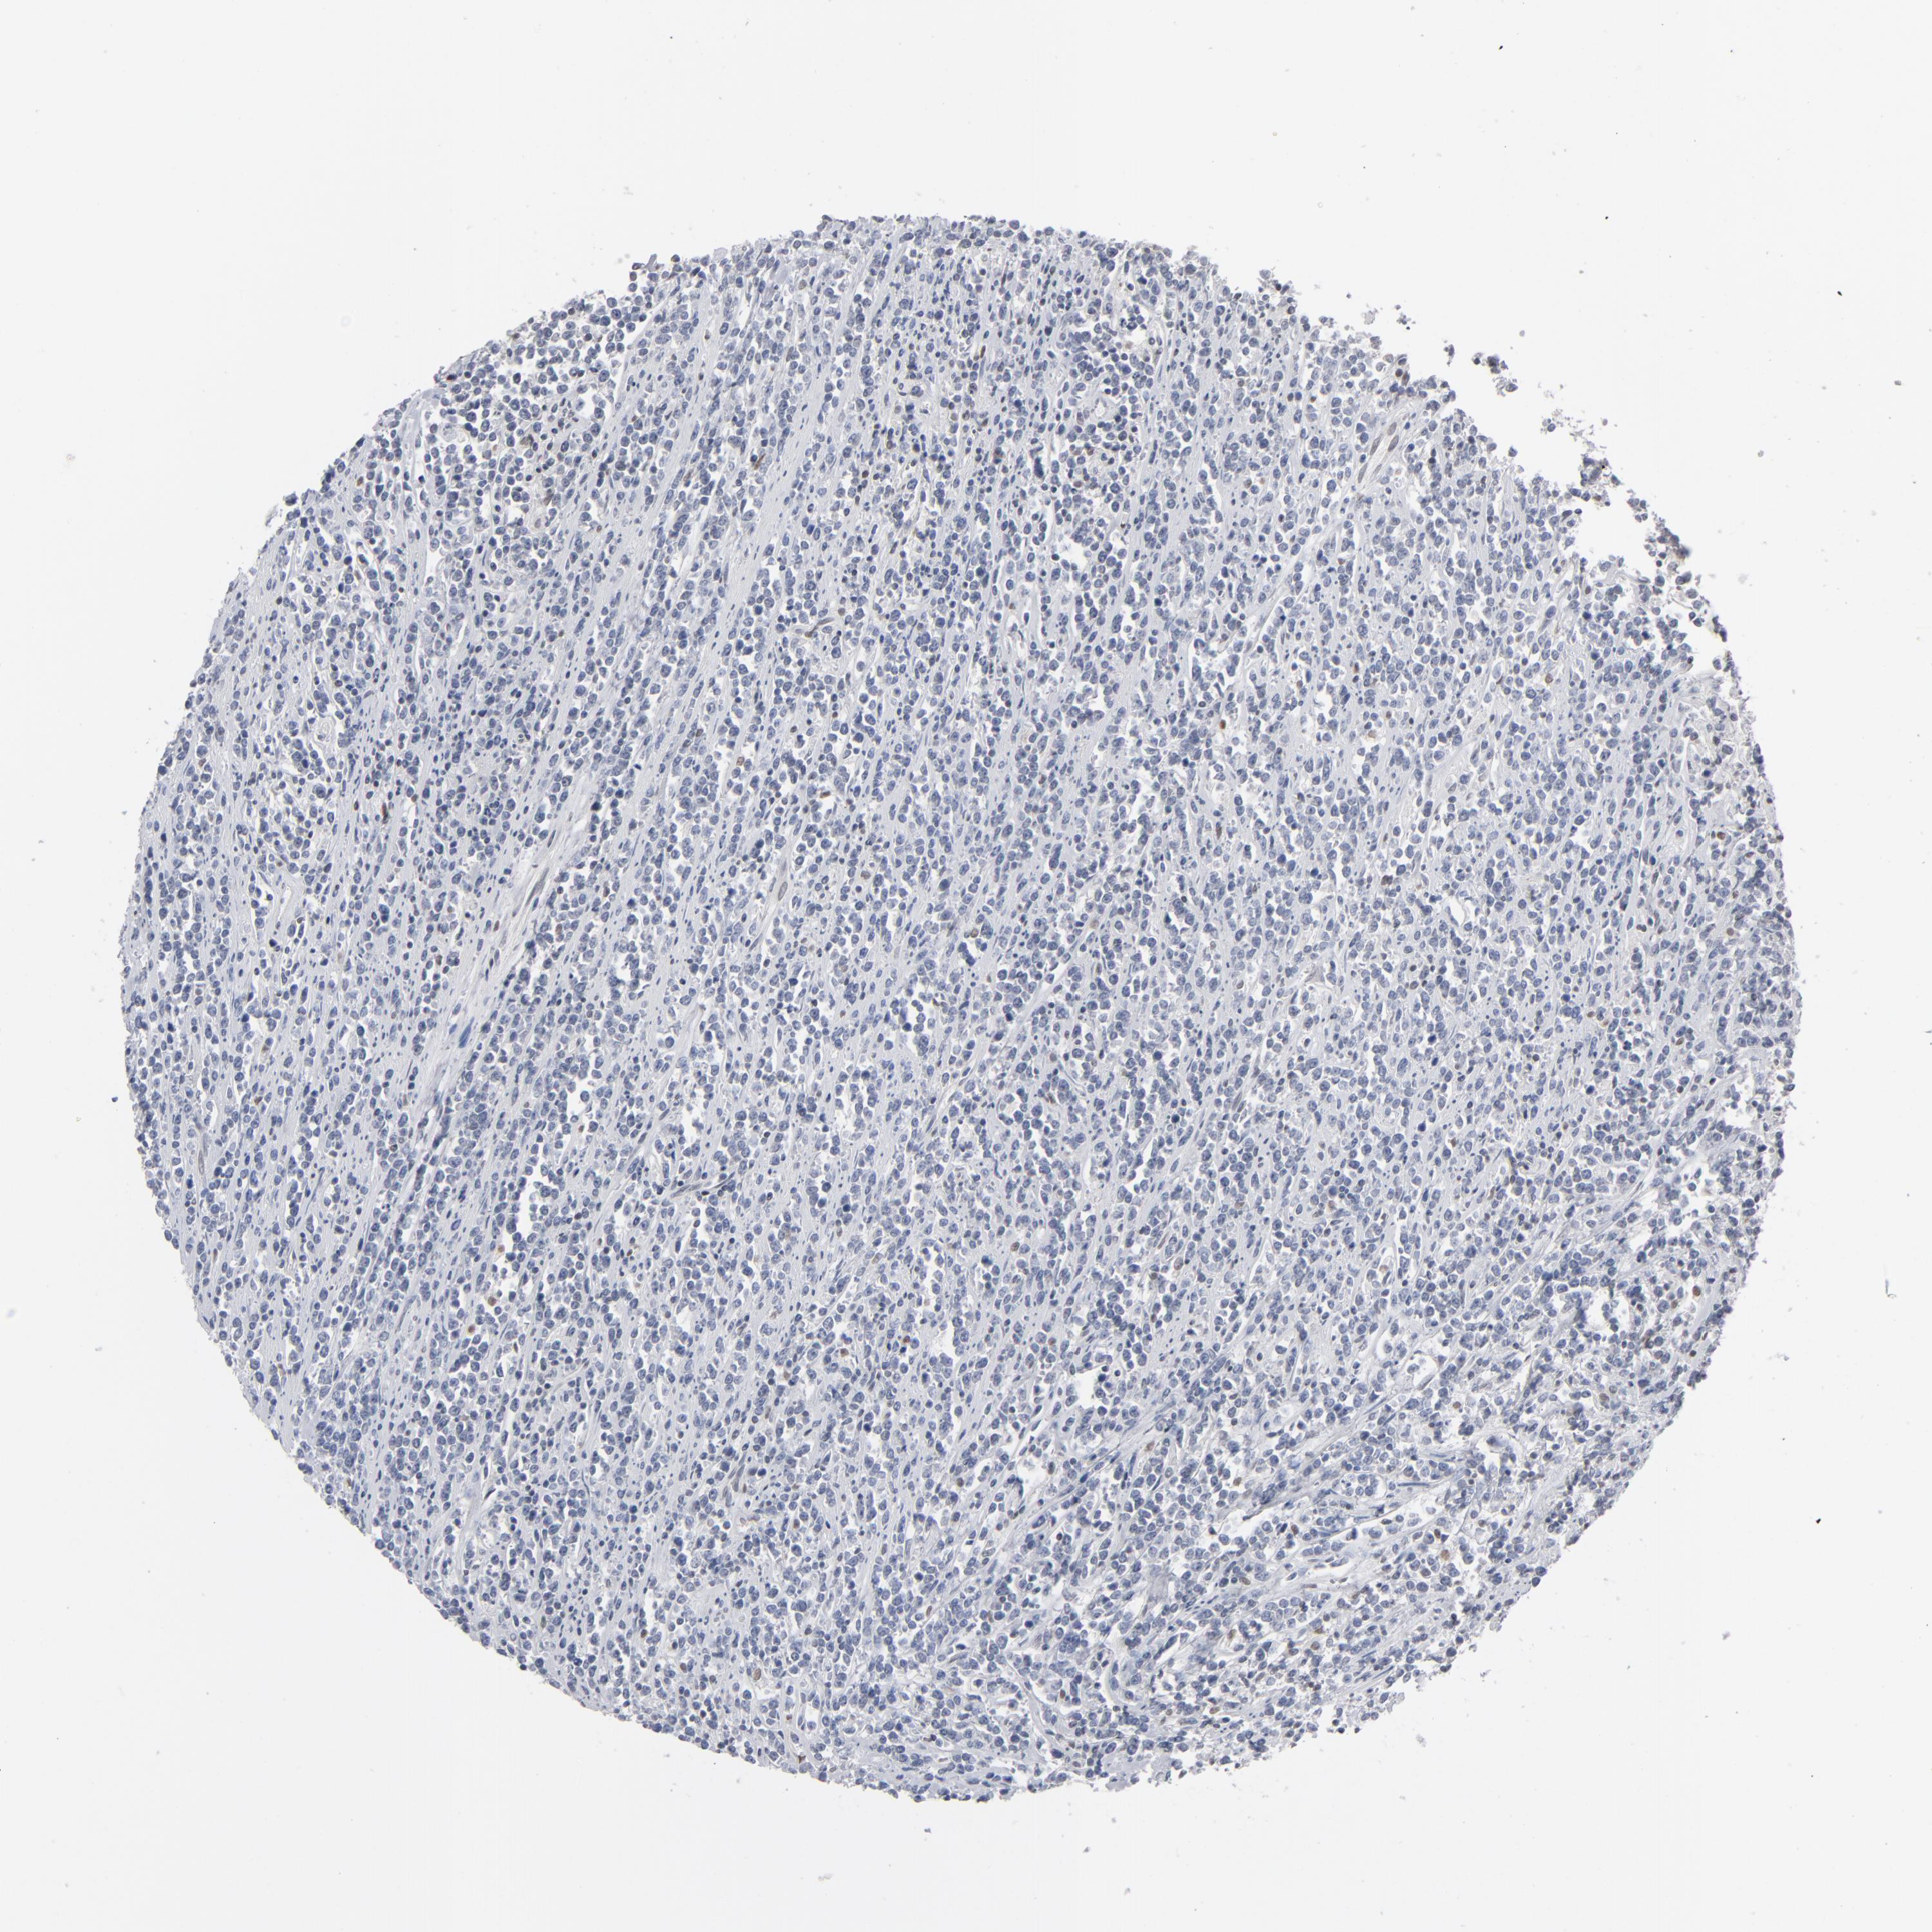

Antibody HPA001862

Staining

High

Medium

Low

Not detected

Intensity

Strong

Moderate

Weak

Negative

Quantity

>75%

75%-25%

<25%

None

Location

Nuclear

Cytoplasmic/membranous

Cytoplasmic/membranous,nuclear

Malignant lymphoma, non-Hodgkin's type, High grade